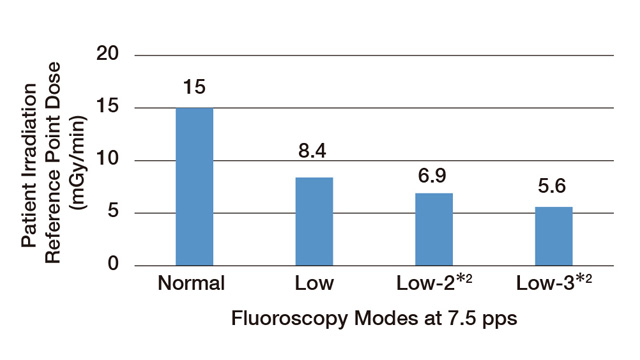

放射科 劳动者健康安全机构 熊本劳灾医院

荒木 裕至

2017

报道

太田纪念医院,日本